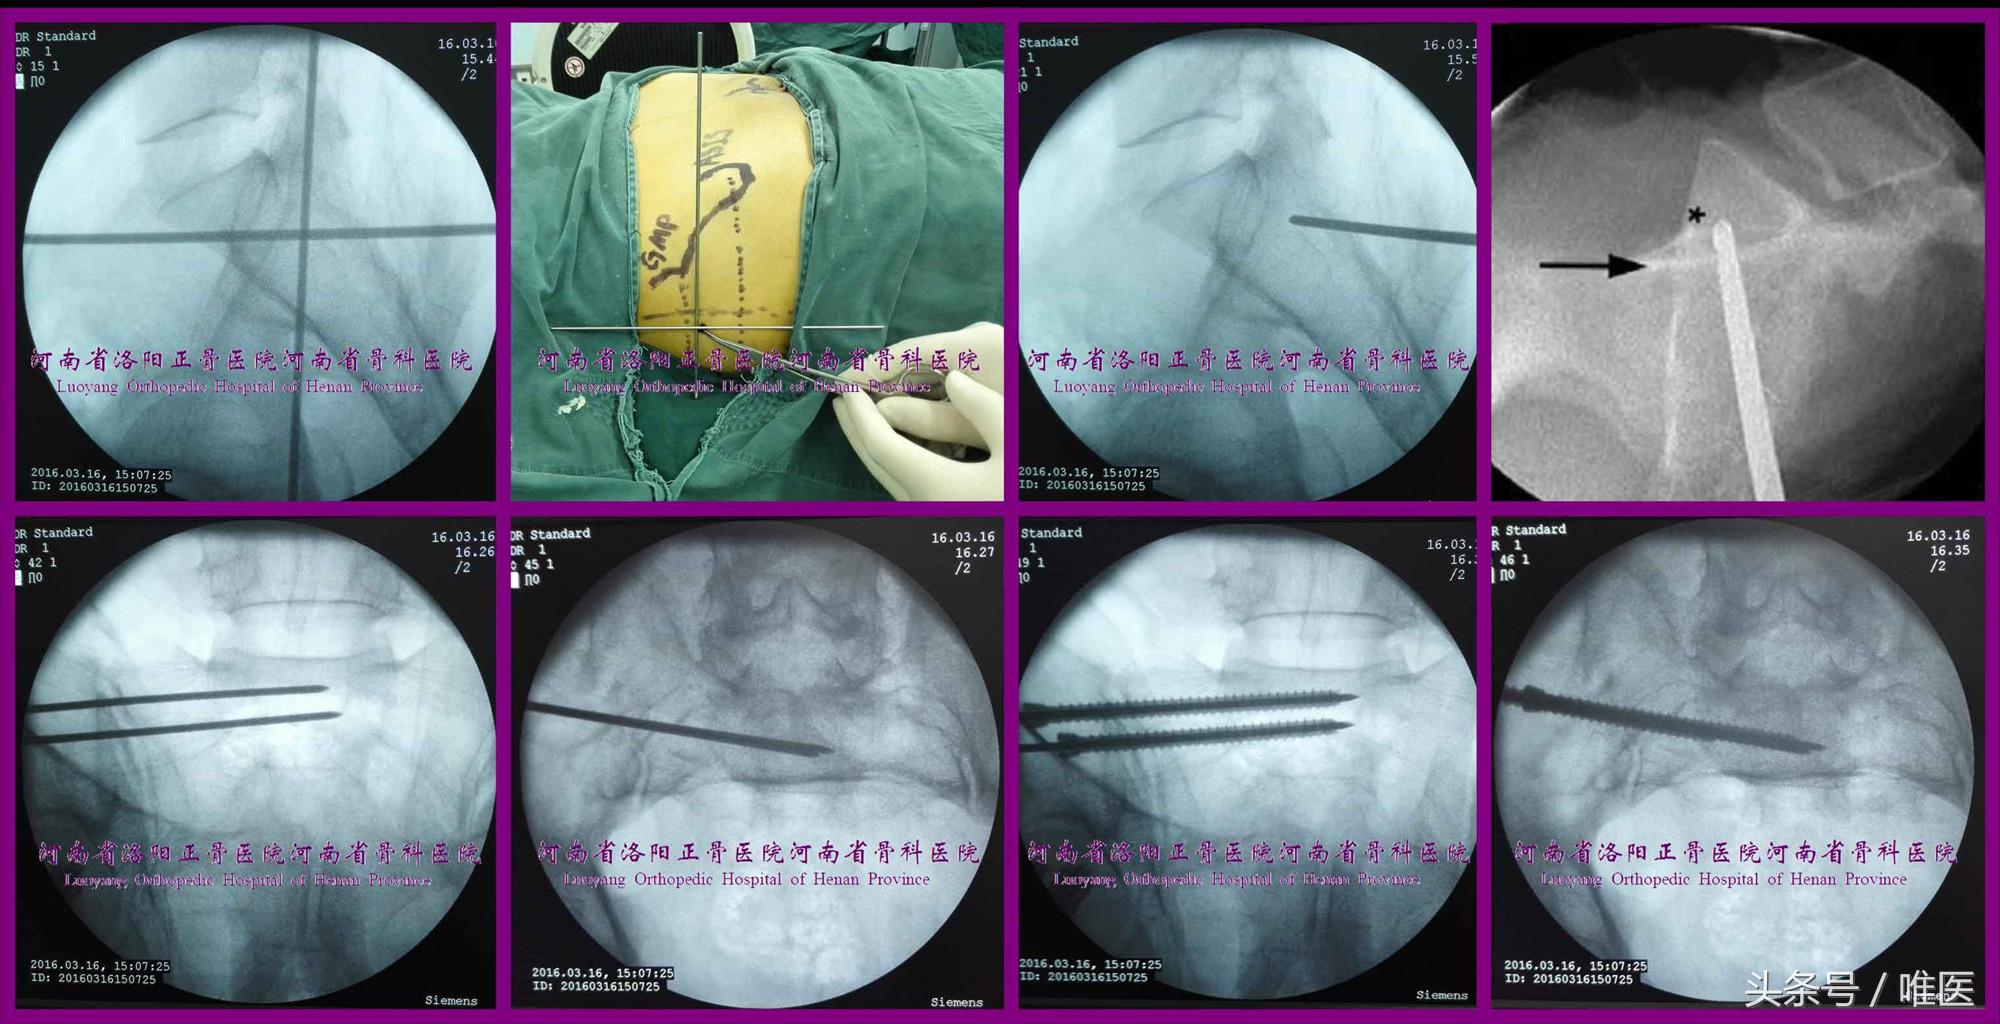

1. 骶1骶髂螺钉的置入技术

术前,通过上述测量方法对骨盆轴向CT进行测量,确定上骶段的类型、骶1椎体及侧块内平向及斜向通道的大小。(图12)

(3)变异型上骶段

①确定进钉点:根据术前骨盆轴向CT测量结果透视出非标准的骶骨侧位像或椎体侧块轴位像,将导针的进钉点确定在上述图像所示的椭圆形的安全通道内。

②调整导针:将导针调整成一个点后轻浅打入骨质。

③确定导针的深度及指向:导针在骨盆出口位上应位于骶1骶前孔的头端、上终板的尾端及骶1椎体内,在骨盆入口位上需要在骶1椎体及其侧块的前缘线的后侧。如未能将导针调整并维持成点状,则在导针行进过程中(特别是在骨盆出入口位上导针尖位于“八”字形骶神经根管的外缘时)需间断透视非标准的骶骨侧位像或椎体侧块轴位像,确定导针的尖端在椭圆形安全区域内。

④置入骶髂螺钉:同上。

图12. 变异型上骶段骶1骶髂螺钉置入示例(末列第一张图片引自参考文献21)。